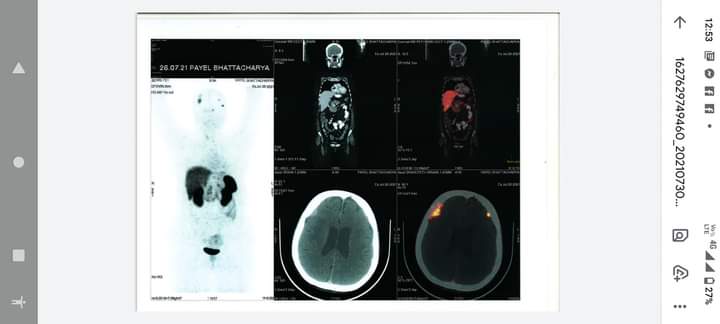

Multiple dural based DOTANOC avid enhancing nodular and plaque-like lesions noted bilaterally, largest along right frontal bone measuring approximately 2.1 x 1.0 cm SUVmax 5.23 with adjacent erosion along the inner table of right frontal bone. Other small nodular enhancing lesions noted along left frontal lobe measuring 6 mm SUVmax

3.78, left temporal lobe 7 mm SUVmax 8.06, right temporal lobe measuring 8 mm SUVmax

1.73, left parasellar region adjacent to superior orbital fissure measuring approximately 7 mm

SUVmax 3.97. Few specks of calcification noted in splenic parenchyma.

In a known case of VHL syndrome; PET/CT scan findings reveal multiple DOTANOC avid

(somatostatin receptor expressing) dural based nodular and plaque-like lesions as

described.